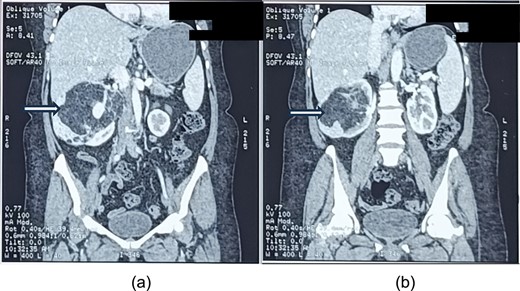

On contrast-enhanced computed tomography (CECT) of the abdomen, there was a large (size ~9.0 × 13.7 × 8.2 cm, APXTRXCC), well defined heterogeneous predominantly hypodense lesions with a large fat component with CT value of fat (−45 to −60) and an enhancing solid part with tortuous vessels at the periphery of lesion arising from the interpolar region of right kidney causing architectural distortion of most of the renal parenchyma (Fig. 1a and b), diagnosed as AML.

a and b showing abdominal CT scan cuts, showing mixed density mass arising from the right kidney (white arrows).

The lesion was causing mass effect on the inferior vena cava posteriorly, 1st and 2nd part of duodenum, head of the pancreas displacing them anteriorly and right renal vein anteromedially. There were no clinic-radiological features of tuberous sclerosis complex (TSC).